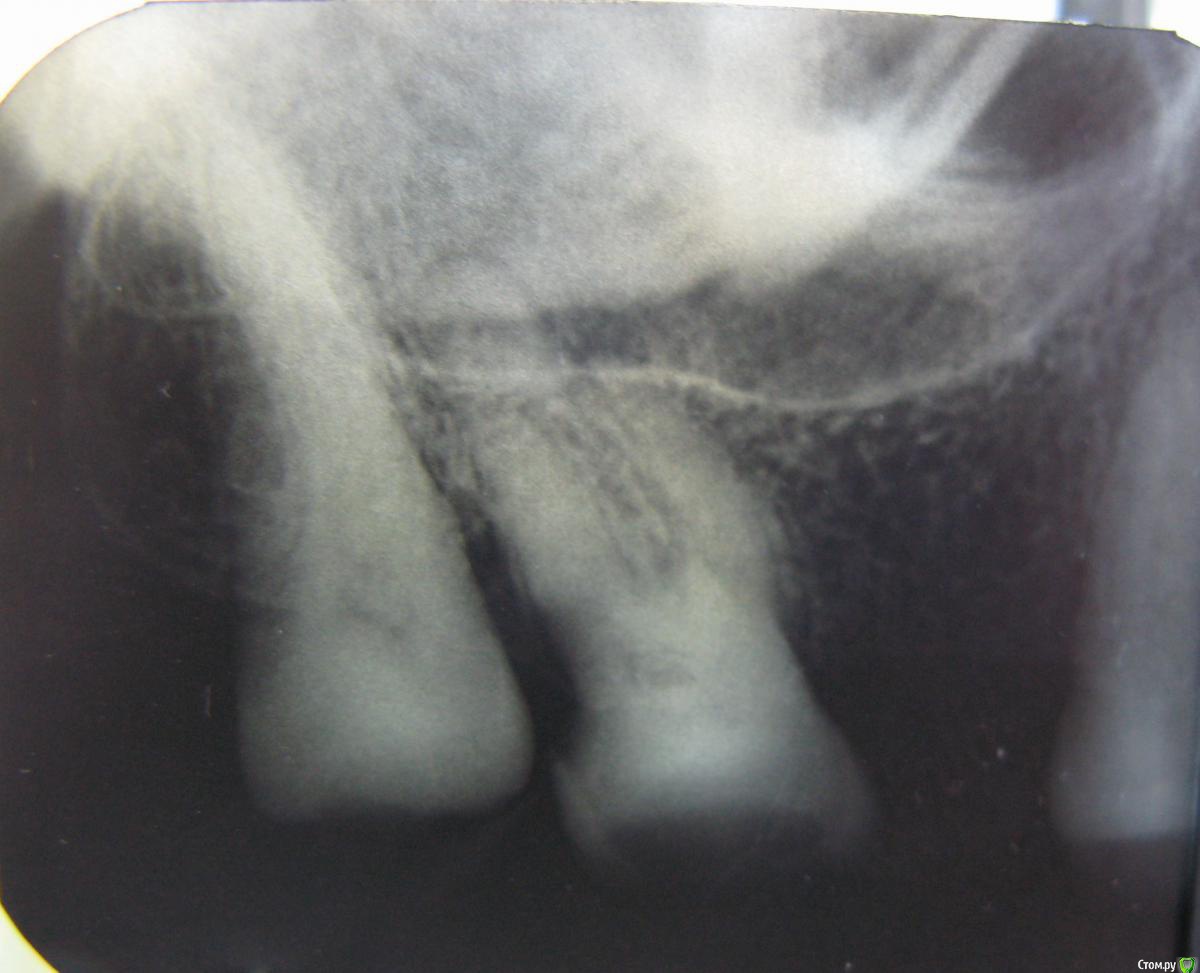

vica17 Опубликовано 11 октября, 2015 Поделиться Опубликовано 11 октября, 2015 (изменено) Добрый день.Прошу специалистов проконсультировать по 27-му зубу.Два месяца назад пошла к доктору для лечения, поставлен был пульпит, зуб рассверлен, установлено, что нервы уже мертвые (был большой многолетний карман со стороны 28 зуба), по запаху доктор определил воспалительный процесс, чистились каналы, заложено лекарство (какое - не знаю). Затем через две недели открыли каналы и установили, что в небном канале есть еще воспаление, при прочистке этого канала было больно и ощущение укола, поставлена временная пломба на 1 месяц. Это было 18 августа. Через 2 недели начался гайморит, потом ставили синусит, пропила сначала 5 дней Цифран СТ, потом через 2 недели назначили Амоксиклав 625мг 7 дней. Анализы отличные, из носа ничего не текло и не течет. Может синусит и не из-за зуба, хотя раньше никогда таких проблем не было, ЛОР определенно не утверждает ничего. Сейчас осталась небольшая ломота в носу с левой стороны (там где зуб). С зубом теперь не знаю, что делать. Была на консультации в двух клиниках (не там, где лечила). Везде сказали, что кариес не убран "зачем лечили каналы, не убрав кариес?". Рекомендации - одна - удалять, другая - можно попробовать полечить с микроскопом, но без гарантии. Зуб до манипуляций не болел совсем, теперь ощутимо и немного болезнено боковое нажатие, хотя накусывание не больно, жевать им могу нормально. Немного ломит скула, но это может остатки от ринита-синусита.Пожалуйста, посоветуйте, есть ли смысл спасать зуб, или шансов нет?Снимок до начала лечения Снимок после двух чисток каналов, пломба временная Заранее благодарна за консультацию. Изменено 11 октября, 2015 пользователем vica17 Ссылка на комментарий

sydnik Опубликовано 11 октября, 2015 Поделиться Опубликовано 11 октября, 2015 здравствуйте!на обоих снимках каналы не лечены!может перепутали чего! 2 Ссылка на комментарий

vica17 Опубликовано 11 октября, 2015 Автор Поделиться Опубликовано 11 октября, 2015 здравствуйте!на обоих снимках каналы не лечены!может перепутали чего!Нет не перепутала, чистили 2 раза, положили лекарство, но не пломбироали еще. Из-за синусита остановилась в лечении. Ссылка на комментарий

vica17 Опубликовано 11 октября, 2015 Автор Поделиться Опубликовано 11 октября, 2015 Наверное я неправильно указала, каналы два раза чистили, но не пломбировали окончательно. Сейчас временная пломба и кариес остлся, как и был с самого начала. Не знаю что теперь с этим делать. Ссылка на комментарий

Л Ю С Я Опубликовано 11 октября, 2015 Поделиться Опубликовано 11 октября, 2015 Если хотите сохранить зуб 2.7: Удалите 2.8Сделайте снимок 3D( компьютерная томограмма)Лечитесь у специалиста, использующего в работе увеличение. Перед лечением каналов доктор должен обязательно убрать кариесПосле успешного лечения защитите зуб коронкой 1 Ссылка на комментарий